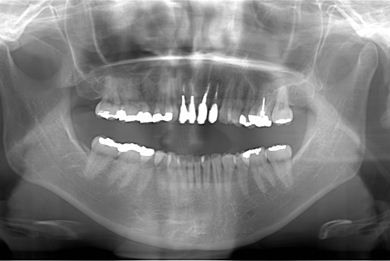

セラミック治療+歯肉歯槽骨整形手術

治療内容 オールセラミッククラウン4本(オールセラミック用土台4本)、歯肉歯槽骨整形手術

治療前

• 治療前